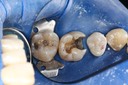

Ted Kanamori #29 - 30 pre-op